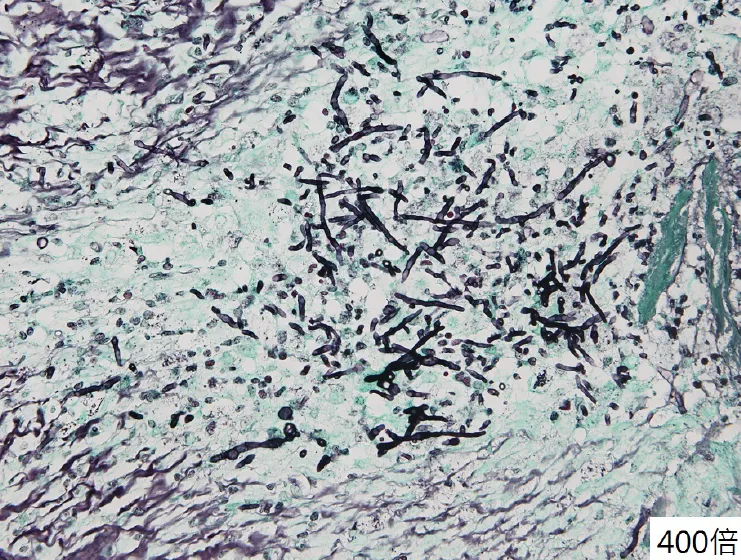

【109-2 醫學(三) 第60題】60歲糖尿病人因右眼視力模糊,鼻腔有黑色分泌物來住院,經耳鼻喉科開刀病理化驗結果如附圖,則下列何者是最可能的致病菌?

詳解

破題關鍵

這題的解題核心在於將糖尿病患者的臨床表現(鼻腔黑分泌物、視力模糊)與病理切片中真菌的形態學特徵結合判斷。圖片中清晰可見有分隔(septate)且呈急性角(約45度)分枝的菌絲,這是麴菌(Aspergillus)的典型病理特徵。

選項拆解